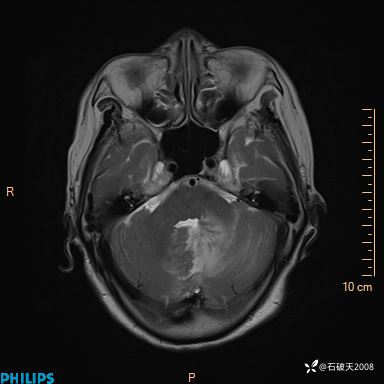

T2